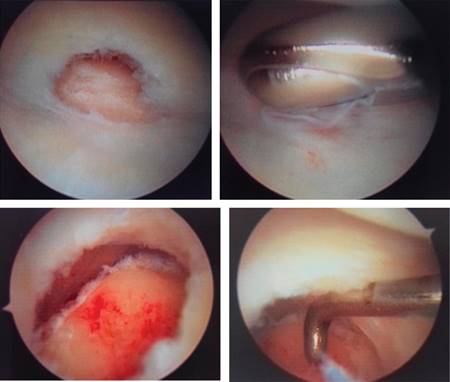

El artroscopio es introducido en portal 3-4 mediante técnica estándar, la salida de la solución fue obtenida colocando aguja hipodérmica número 18 a través del portal 6R o 6U. El recorrido artroscópico se realizó de rutina desde el portal mediocarpal hasta el portal cubital, visualizando sinovitis con ruptura central del fibrocartílago triangular (Figura 3).

Figura 3: Evaluación artroscópica del fibrocartílago triangular y realización de procedimiento de Wafer.

Realizando procedimiento a través de portal 6R, desbridando la ruptura central del fibrocartílago triangular con rasurador mecánico 2.9 mm hasta dejar bordes estables, con fresa redonda 3.0 mm (Arthrex) es usada para remover todo el cartílago articular distal del cúbito, así como los quistes subcondrales a través del defecto central ante desbridado del fibrocartílago triangular. Con la misma fresa se realiza el acortamiento del extremo distal del cúbito, con el ayudante que realiza movimiento de rotación de la muñeca desde la supinación hasta la pronación completa, para así realizar una adecuada exposición y resección del cúbito distal mientras se protege la inserción del fibrocartílago triangular en la base del estiloide cubital.

Se realiza sinovectomía, se extraen los cuerpos libres articulares, se realiza hemostasia con ayuda de radiofrecuencia. Al final de la cirugía se obtuvo una varianza cubital de neutral a -2 mm, se cierran los portales con prolene 0000, y se inmoviliza con férula antebraquiopalmar.